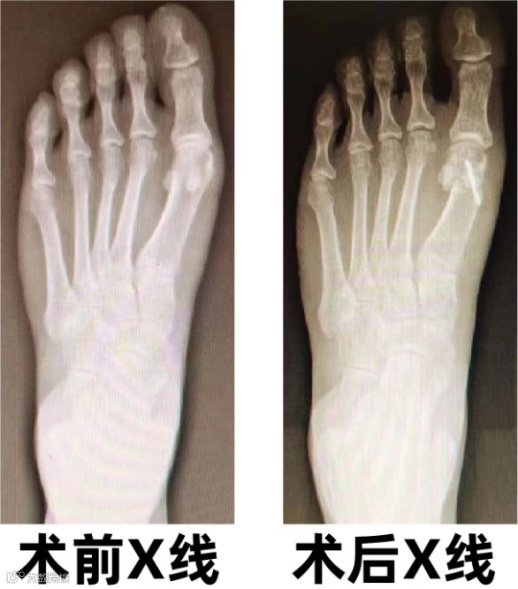

手术治疗:严重情况下,建议手术治疗,因为拇外翻通常持续进展。

中心医院拇外翻采取微创小切口矫形手术,术后当天即可行走,不影响生活工作。

部分病例术前术后对比图